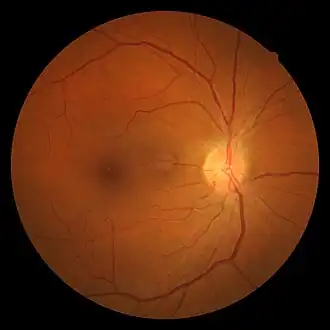

| Hypertensive retinopathy with AV nicking and mild vascular tortuosity | |

- Arteriolar changes, such as generalized arteriolar narrowing, focal arteriolar narrowing, arteriovenous nicking, changes in the arteriolar wall (arteriosclerosis) and abnormalities at points where arterioles and venules cross. Manifestations of these changes include Copper wire arterioles where the central light reflex occupies most of the width of the arteriole and Silver wire arterioles where the central light reflex occupies all of the width of the arteriole, and "arterio-venular (AV) nicking" or "AV nipping", due to venous constriction and banking.